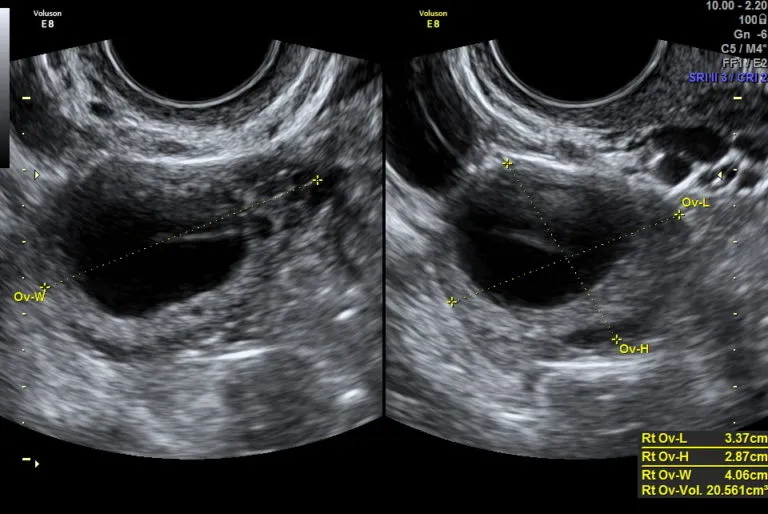

Optymalne "okienko czasowe" w cyklu na wykonanie USG poowulacyjnego

Moje doświadczenie podpowiada, że najlepszy moment na wykonanie USG w celu potwierdzenia owulacji to kilka dni po przewidywanym terminie jajeczkowania. Przy regularnych cyklach trwających około 28 dni, owulacja zazwyczaj przypada na 14. dzień. W takim przypadku, optymalne "okienko czasowe" na badanie poowulacyjne to między 16. a 22. dniem cyklu. W tym czasie ciałko żółte jest już dobrze uformowane i widoczne, a ewentualny płyn w zatoce Douglasa jest łatwiejszy do zlokalizowania. To pozwala mi na pewne i jednoznaczne potwierdzenie, że owulacja się odbyła.